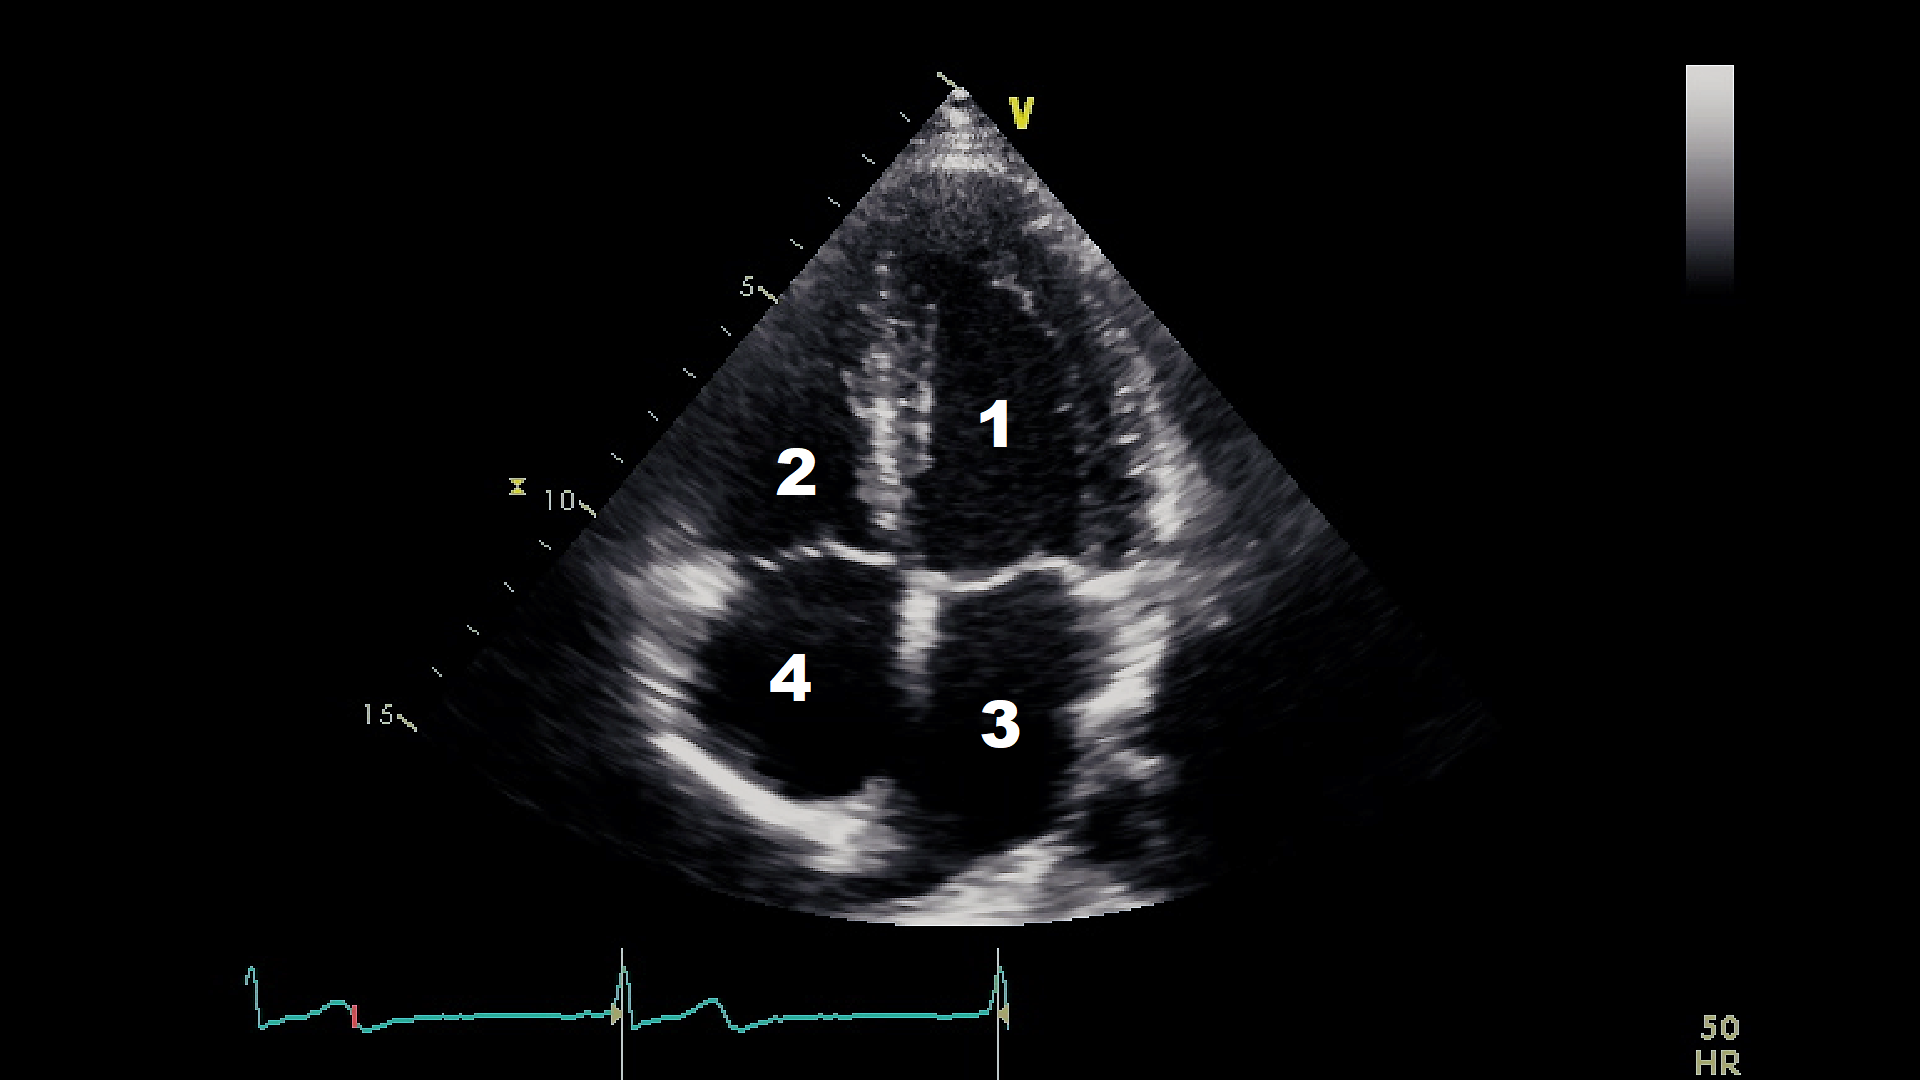

This work focuses on performing early MI detection by learning RWMA of the LV wall in the A4C view echocardiography. Figure 2 shows a captured frame representing the A4C view, which consists of four distinct heart chambers, numbered from 1 to 4, where 1 identifies the LV, 2 to 4 identifies the Right Ventricle, the Left Atrium, and the Right Atrium, respectively.

Refer to caption

Figure 2: Apical four-chamber view. The numbers from 1 to 4 marking the four different chambers correspond respectively to the LV, the right ventricle, the left atrium, and the right atrium